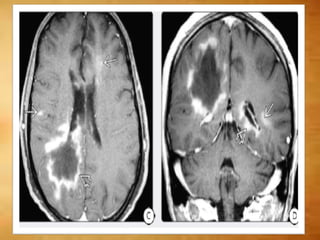

MARBURG DISEASE

Imaging shows diffusely disseminated disease

o Large cavitating lesions

○ Incomplete enhancing rim

○ Multiple other patchy enhancing foci

26/M with short H/O visual disturbance and upper extremity weakness

MARBURG DISEASE Imaging showsdiffusely disseminated disease o Large cavitating lesions ○ Incomplete enhancing rim ○ Multiple other patchy enhancing foci

• 48.

26/M with shortH/O visual disturbance and upper extremity weakness